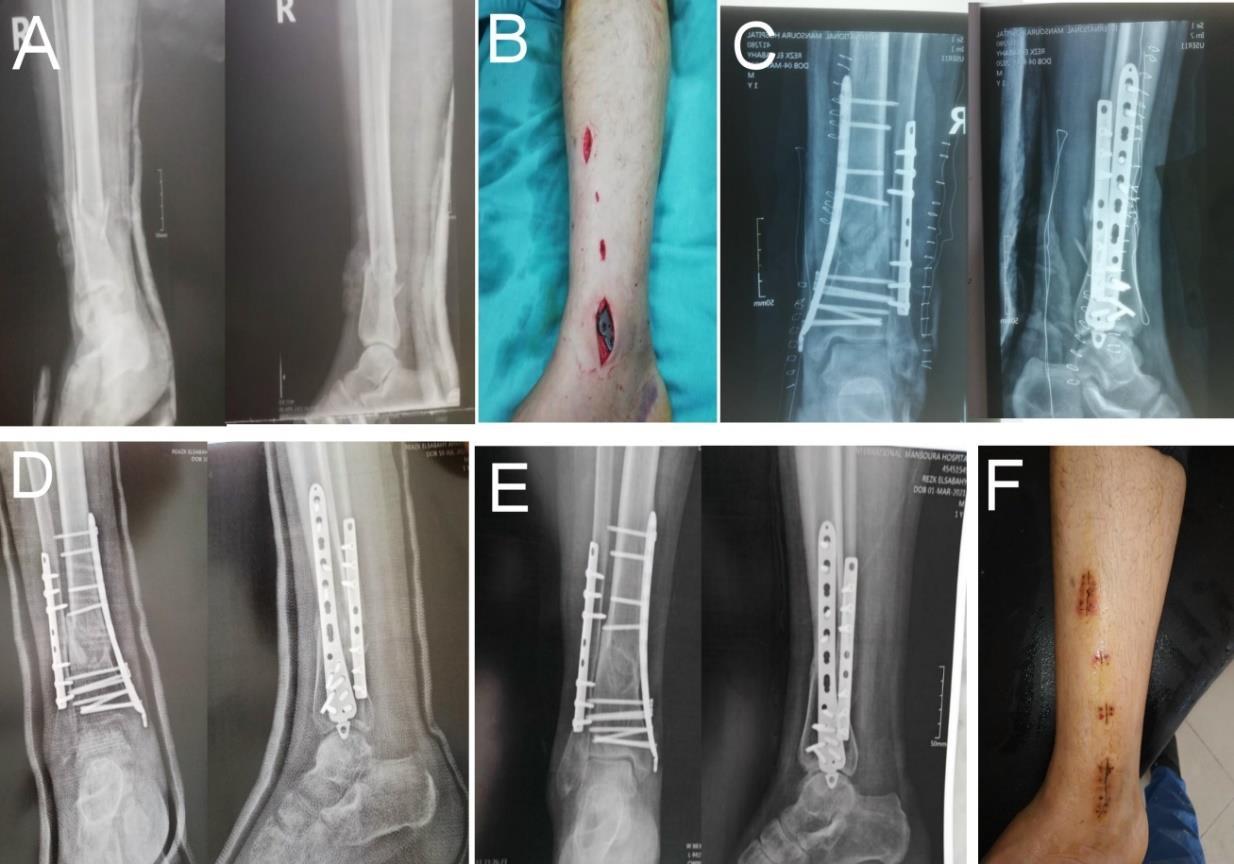

Case 1: Female patient 32 years old was presented by trauma due to road traffic injury to the left leg with associated fracture fibula. The patient was operated on 9th day of injury under spinal anesthesia. She had no past history of medical illness. No intraoperative or postoperative complication. Her result was excellent according to ankle hindfoot scale (Fig 1).